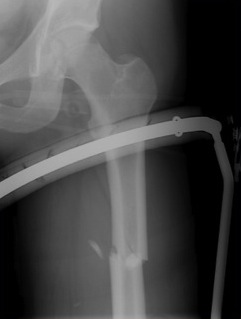

2. NOF (Neck of Femur) + Femoral shaft fracture

Must pay attention first to meticulous NOF ORIF

Options

1. Pin and Plate NOF / Retrograde Nail

2. Pin and Plate NOF / Plate femur

3. Reconstruction Nail

- difficult to anatomically reduce NOF

- increased incidence NOF non union

Difficult scenario

- antegrade IMN in place before diagnosis of NOF fracture

- if undisplaced, can place screws anterior to nail

- if displaced must remove nail

Results

Ostrum et al. CORR 2014

- 95 cases treated with proximal screws / sliding hip screws inserted first

- retrograde IMN second

- 98% union rate femoral neck

- 91% union rate femoral shaft

https://www.ncbi.nlm.nih.gov/pmc/articles/PMC4117883/pdf/11999_2013_Article_3271.pdf